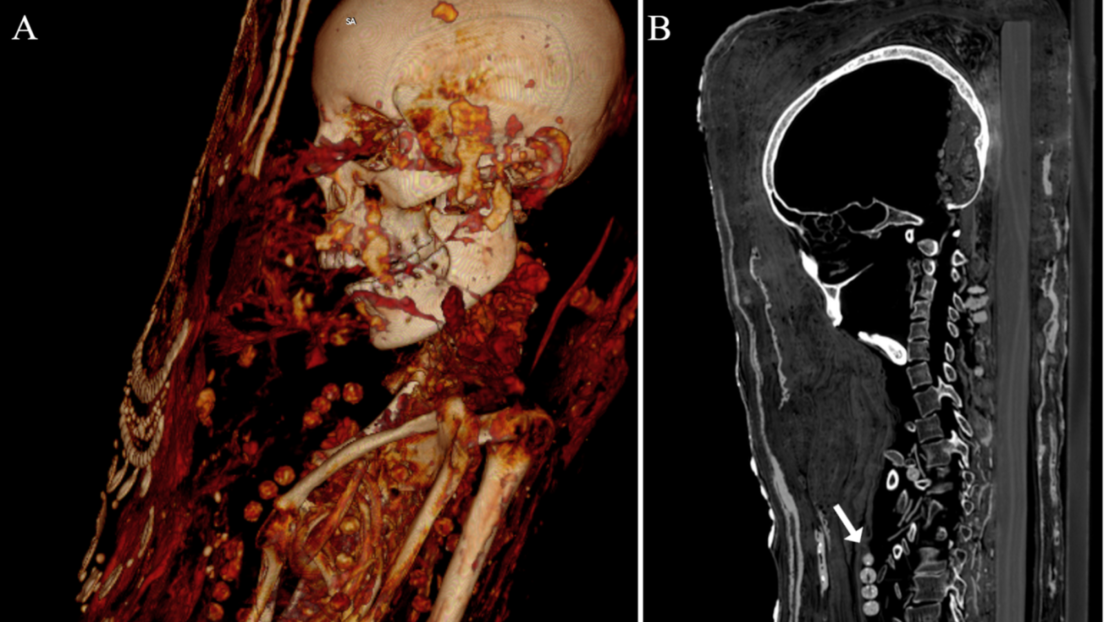

Las momias, que se corresponden con un hombre adulto, una mujer de mediana edad y otra mujer joven, son las únicas cubiertas de estuco que se han encontrado en la antigua necrópolis de Saqqara. En el proceso, los cuerpos se colocaban sobre tablas de madera antes de se envueltos en tela, yeso y oro, añadiéndose en la superficie un retrato de cuerpo entero.

Además, los expertos identificaron cuentas de collares, una horquilla y objetos de metal denso, como sellos de plomo, clavos y dos monedas o medallones, con los que fueron enterrados los individuos.